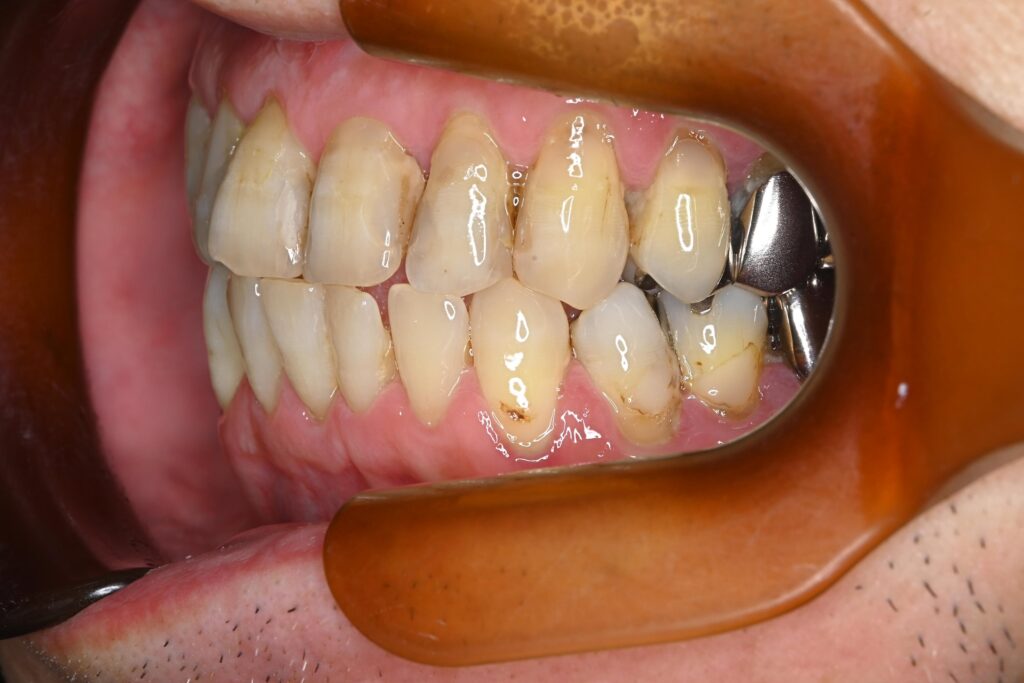

初診時の口腔内の状態:

お口全体に虫歯や歯周病の原因となるプラーク(歯垢)が多く付着していました。右上奥歯は重度の虫歯で歯冠部(歯の頭)が失われており、左下奥歯は過去の治療箇所から細菌が入り込み、根の先に炎症が起きている状態でした。

また、左右の奥歯にはWSD(楔状欠損)があり、知覚過敏も見られました。

単なる虫歯だけでなく、「切端咬合(せったんこうごう)」という噛み合わせの不調和が根本的な問題であると診断しました。この噛み合わせにより奥歯に過度な負担がかかり、知覚過敏や歯の損傷を引き起こしていました。